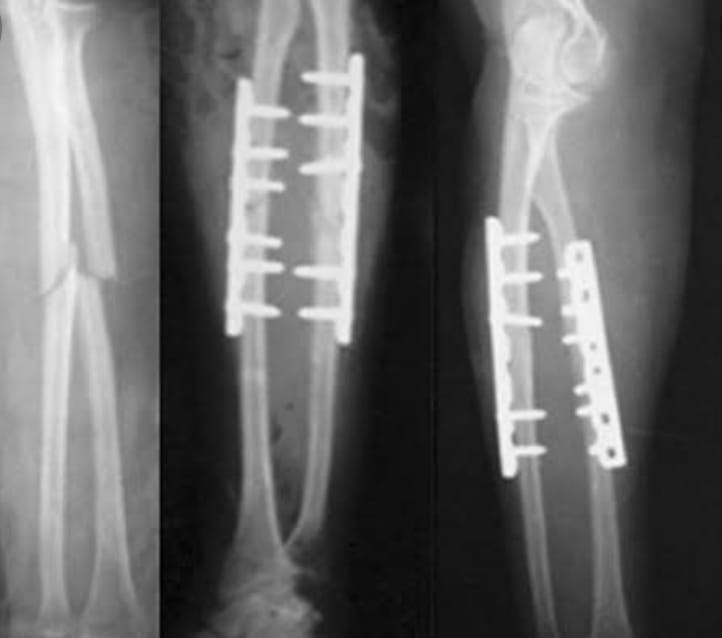

The Veer Hospital provides effective and high-quality healthcare services with 20+ departments, 16 special units and 50+ physicians. We offer an up-to-date medical approach in an ethical and reliable environment. We maintain our reputation in the health sector with our experienced medical staff who continuously improve qualified healthcare with an uncompromising focus when it comes to proficiency and academic values.